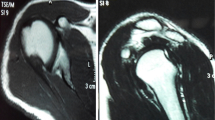

Connolly first described an open procedure of filling a Hill-Sachs defect with infraspinatus and capsule tenodesis, together with a Bankart repair [10]. This technique works by converting an intra-articular defect into an extra-articular one and thus preventing the defect from engaging at the anterior glenoid rim. Furthermore, there is a check-rein effect on the humeral head, effected by the fixed infraspinatus tendon and posterior capsule. Wolf et al. termed the procedure remplissage when they performed the procedure arthroscopically, placing suture anchors into the valley of the Hill-Sachs defect and passing the sutures posteriorly through the infraspinatus tendon and capsule [11]. Cadaveric studies have shown that medium sized Hill-Sachs lesions without glenoid bone loss can be successfully treated with the remplissage procedure if combined with Bankart repair [12, 13]. In recent years, clinical studies have already reported good functional outcomes with minimal loss of shoulder range of motion [14–16]. Although, filling of the Hill-Sachs defect by infraspinatus tendon and capsule on post-operative scans has been demonstrated [17], there are no studies in the literature investigating the amount of infraspinatus tendon coverage over the defect zone produced by different techniques.

Area of M. infraspinatus tendon coverage over Hill-Sachs defect

Semi-quantitative analysis of defect coverage patterns showed increased compression around and between the insertion points of each anchor and the edges of the Hill-Sachs defect for all repair groups (T1, T2, and T3). The main area of compression was located in the center of the bony defect for any repair group.

The mean coverage of M. infraspinatus tendon into the Hill-Sachs defect was largest for the tape technique (T3) with 26.8 %. The pulley technique (T2) revealed a 15.9 % coverage, and the knot technique (T1) a 13.3 % coverage. Area of tendon coverage over defect zone was in T3 significantly larger than in T1 and T2 (p = .03). There was no significant difference between T1 and T2 (n.s.). See Table 2.

Regarding area of tendon coverage over the Hill-Sachs defect, this study showed that the proposed knotless suture tape technique (T3) created a significantly larger area of tendon coverage over the defect zone compared to the two other techniques (T1, T2). The authors are not aware of any literature investigating and reporting on area of tendon coverage over the defect zone after remplissage.